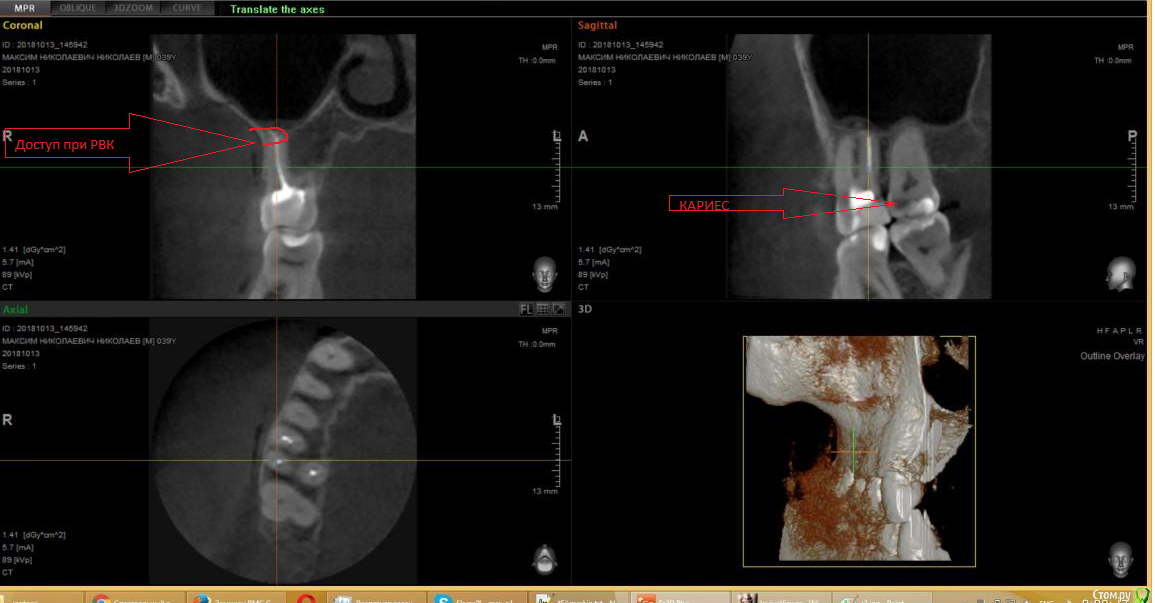

___49___ Опубликовано 5 декабря, 2018 Поделиться Опубликовано 5 декабря, 2018 (изменено) Сначала исключите кариес по контакту в 7 ке( и вообще во всех зубах с этой стороны) , вынуть материал, сохранить зуб и целостность слизистой можно путем резекции верхушки корня - для 6 ки это вполне реально выполнить, но нужно смотреть очно вас и детально КТ , для того чтобы дать однозначный ответ . Имейте ввиду что далеко не все хирурги стоматологи выполняют данную манипуляцию в области 6ок - нужно будет еще искать доктора для которого это вполне рядовая операция а не "эксклюзив". Сомневаюсь, что вся ваша клиника от этого пломбировочного,но.... Изменено 5 декабря, 2018 пользователем ___49___ Ссылка на комментарий

usilitel Опубликовано 5 декабря, 2018 Автор Поделиться Опубликовано 5 декабря, 2018 (изменено) Сначала исключите кариес по контакту в 7 кеУже сделал. вынуть материал, сохранить зуб и целостность слизистой можно путем резекции верхушки корняРезекцию верхушки корня делать принципиально не хочу по многим причинам (главная причина - скорее всего не поможет). Лучше вырву зуб, все равно его рано или поздно нужно будет вырвать. К тому же судя по ощущениям меня беспокоит именно сам зуб, а не материал в гайморовой (зуб сильно реагирует при постукивании). В связи с этим есть несколько вопросов: 1) Можно ли сразу после удаления зуба специально вытолкнуть материал в гайморову пазуху (чтобы он вышел за слизистую, чтобы потом его можно было достать эндоскопом сверху)? 2) Если да - то заживет ли потом дырка в слизистой гайморовой пазухи? (слизистая ведь будет немного нарушена после проталкивания через нее материала, в ней же наверное дырка будет?) 3) Реален ли такой вариант: просто вырываю зуб (материал остается где и сейчас, между перегородкой и слизистой), а потом, если понадобится, мне разрежут десну и вынут этот материал (то есть вынут его сбоку)? Изменено 5 декабря, 2018 пользователем usilitel Ссылка на комментарий

usilitel Опубликовано 6 декабря, 2018 Автор Поделиться Опубликовано 6 декабря, 2018 РВК (резекция) - на мой взгляд наиболее благоприятная по прогнозу операцияЕсли я правильно понимаю - в моём случае РВК нельзя сделать, т.к. чтобы добраться до материала в пазухе - придётся разрезать перегородку между зубом и пазухой. Или нет? Ссылка на комментарий

usilitel Опубликовано 6 декабря, 2018 Автор Поделиться Опубликовано 6 декабря, 2018 1 Разберитесь все таки с кариесом .Сори, это просто снимок старый, этот кариес мне уже убрали. Ссылка на комментарий